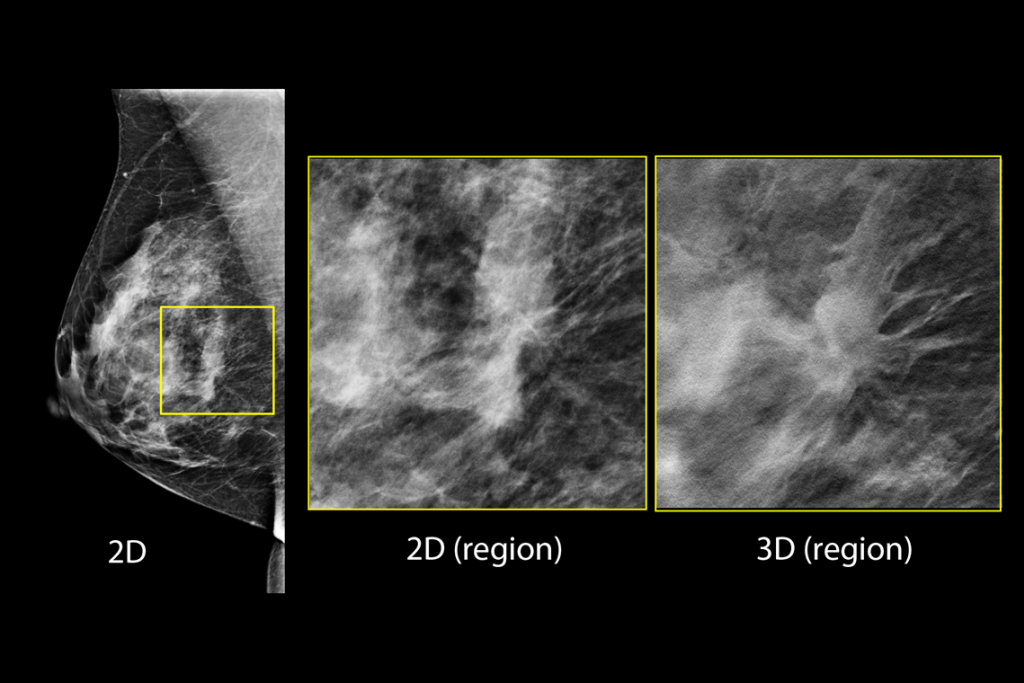

Clinical images of breast scan mammography

Clinical images of breast scan with suspicious Lesion

Clinical images of breast scan

Clinical images of breast scan with fatty breast